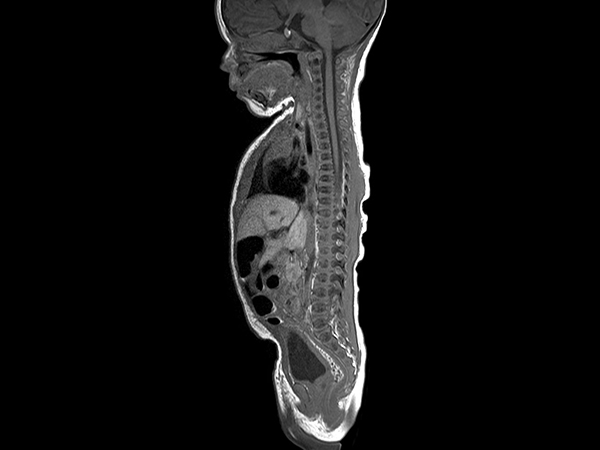

Pediatric Total Spine with spina bifida

Neonatal patient, 5 days old, with spina bifida